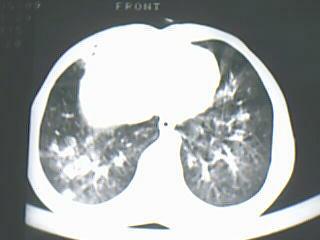

以下是引用随光逐影在2009-8-7 15:40:00的发言:[br]考虑右肺继发性肺结核并右肺上叶空洞形成,两肺支气管播散;不排除右肺上叶空洞内霉菌感染可能。

以下是引用jiangjing在2009-8-7 14:38:00的发言:[br]右上肺张力空洞,酐珞坏死灶,支气管扩张,多发播散灶,纵膈淋巴结显示,胸膜增厚---结核